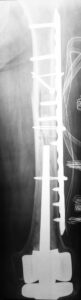

- Η ταξινόμηση των περιπροθετικών καταγμάτων ανάλογα με την περιοχή και τη θέση του κατάγματος σε σχέση με το εμφύτευμα της αρθροπλαστικής.

- Περιπροθετικό κάταγμα. Κάταγμα του οστού σε γειτνίαση με ορθοπεδικό εμφύτευμα. Διακρίνεται το κάταγμα κάτωθεν του εμφυτεύματος.

- Περιπροθετικό κάταγμα ανάμεσα σε δύο εμφυτεύματα με αστοχία της πλάκας οστεοσύνθεσης.